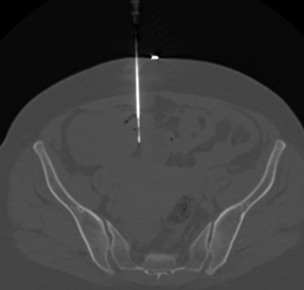

Biopsy of Pelvic soft tissue deposit - Narayana Imaging & Diagnostics